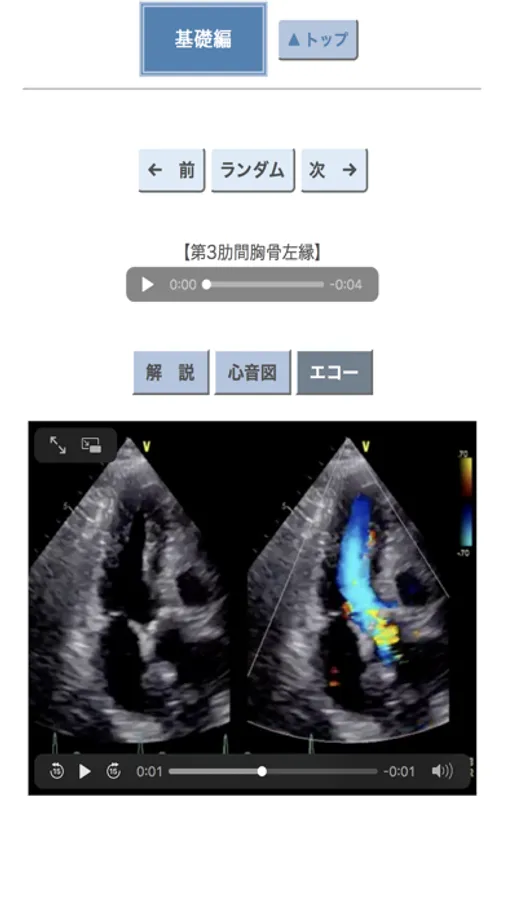

この心臓語が持つ面白さを伝えるために本アプリ「ポケット心音」を作成しました.聴診器の歴史や心音のトリビアも紹介しています.心臓の聴診に興味を持つきっかけになればこれ以上の喜びはありません.